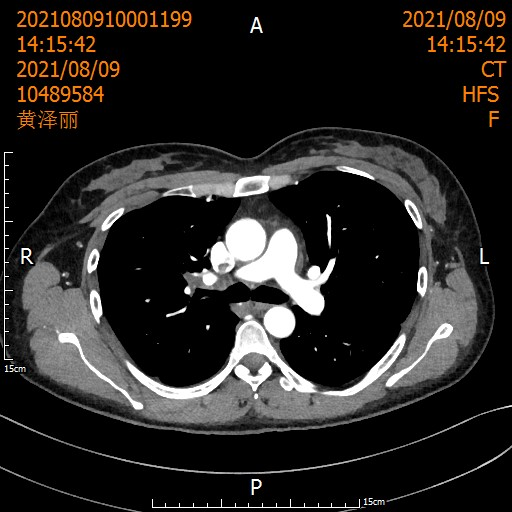

遵循《国际专家共识》,刘浩团队启动了术前2周期化疗联合3周期"卡瑞利珠单抗+紫杉醇/卡铂"治疗。

治疗后患者影像

经过术前新辅助治疗后,医生又为她精心策划了根治性手术,团队紧密配合,顺利完成。

当术后病理报告出炉时,所有人的激动难以言喻: 肺泡上皮增生,间质明显纤维化伴淋巴细胞浸润及淋巴滤泡形成,未见明显肿瘤细胞,切缘阴性,21枚淋巴结0转移——病理完全缓解(pCR)!

从T3到T0,从晚期到根治,这场医患携手创造的奇迹,让整个科室沸腾!